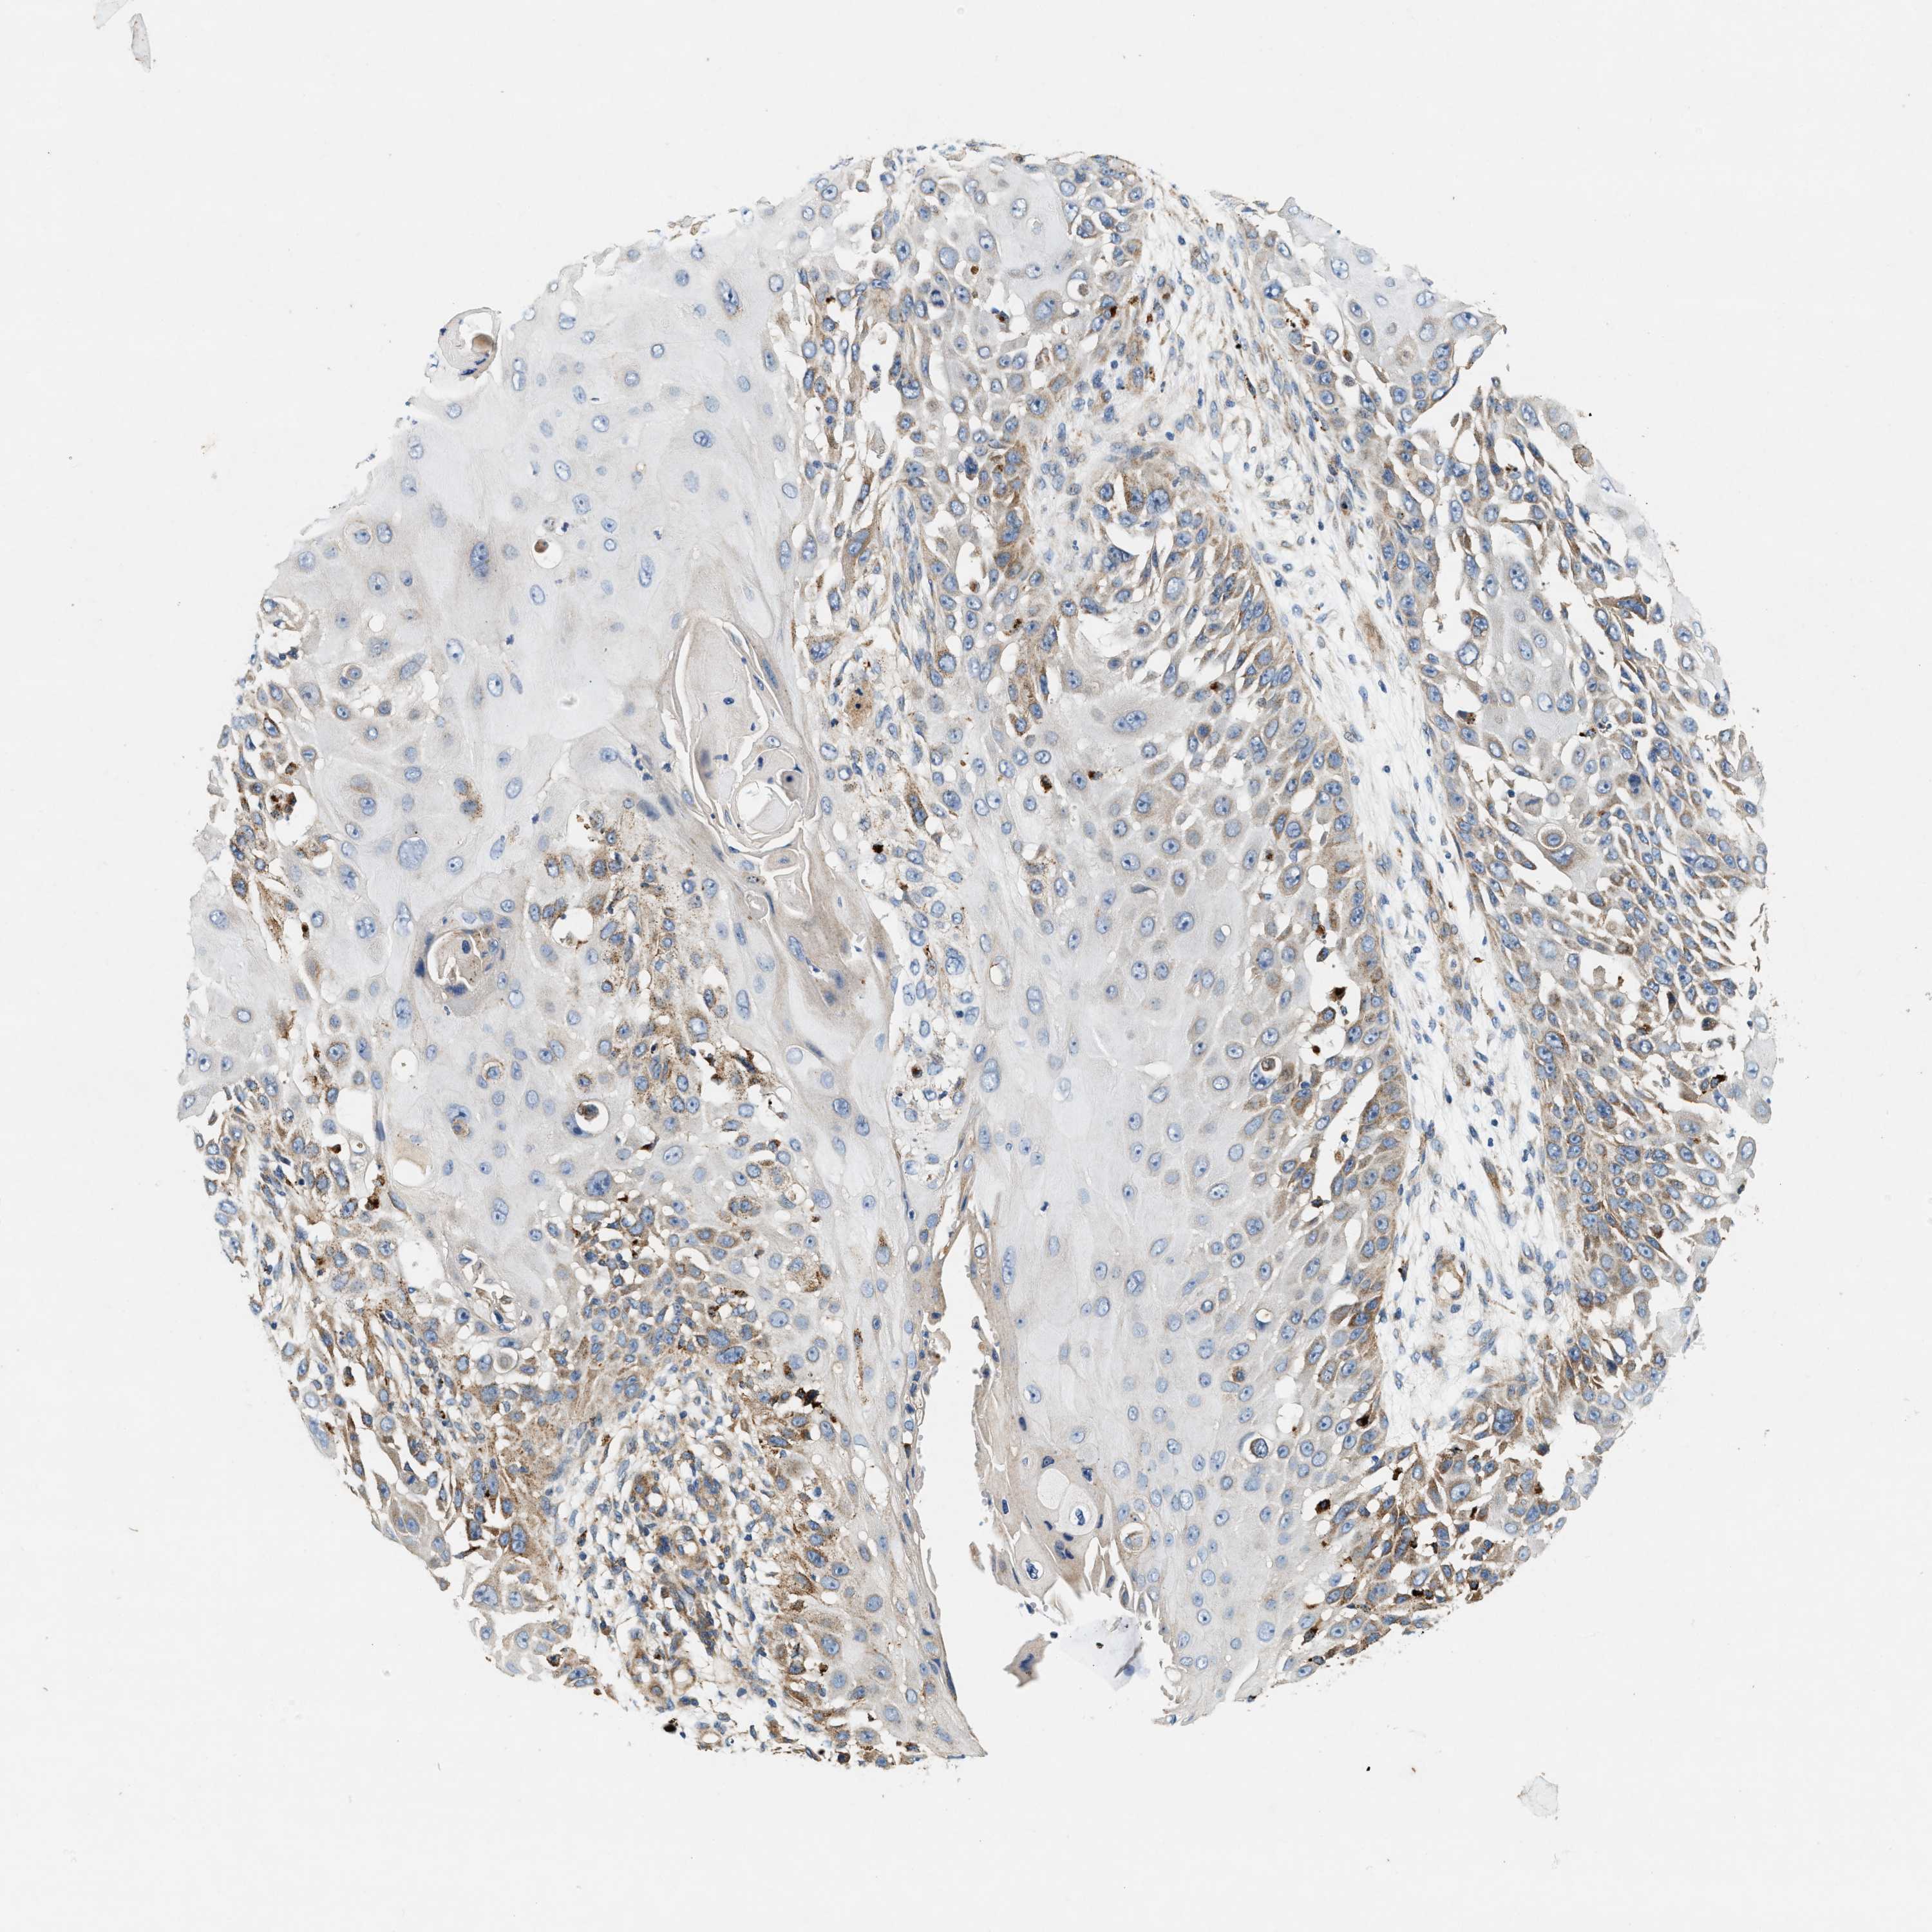

Basal cell and squamous cell cancer

SKIN CANCER - Protein expressioni

A mouse-over function shows sample information and annotation data. Click on an image to view it in a full screen mode. Samples can be filtered based on level of antibody staining by selecting one or several of the following categories: high, medium, low and not detected. The assay and annotation is described here.

Antibody stainingi

Antibody staining in the annotated cell types in the current human tissue is reported as not detected, low, medium, or high, based on conventional immunohistochemistry profiling in selected tissues. This score is based on the combination of the staining intensity and fraction of stained cells.

Each image is clickable and will lead to virtual microscopy that enables deeper exploration of all samples and also displays staining intensity scores, fraction scores and subcellular localization as well as patient and tissue information for each sample.

Antibody HPA016758

Squamous cell carcinoma, NOS